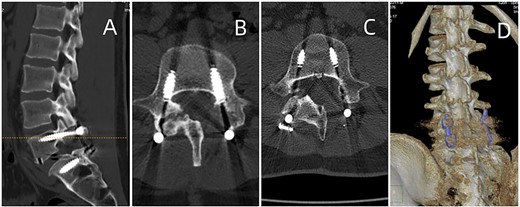

In this study, tophi were identified as areas of low signal intensity on T1-weighted and focal high signal intensity on T2-weighted images. The tophi exhibited heterogeneous marginal enhancement with gadolinium. This case is the first to show radiological evidence of complete resolution of urate deposits in the lumbar region using DECT post TLIF and urate-lowering therapy (Fig. 4). It highlights the efficacy of DECT as a non-invasive imaging modality for assessing treatment response and elucidating the etiology of chronic tophaceous spinal gout-related back pain in patients [13].

Postoperative CT of lumbar fusion surgery, depicted in (A) and (B). Two years postoperatively, DECT (displayed in (C) and (D)) reveals no urate deposition in the lumbar area.